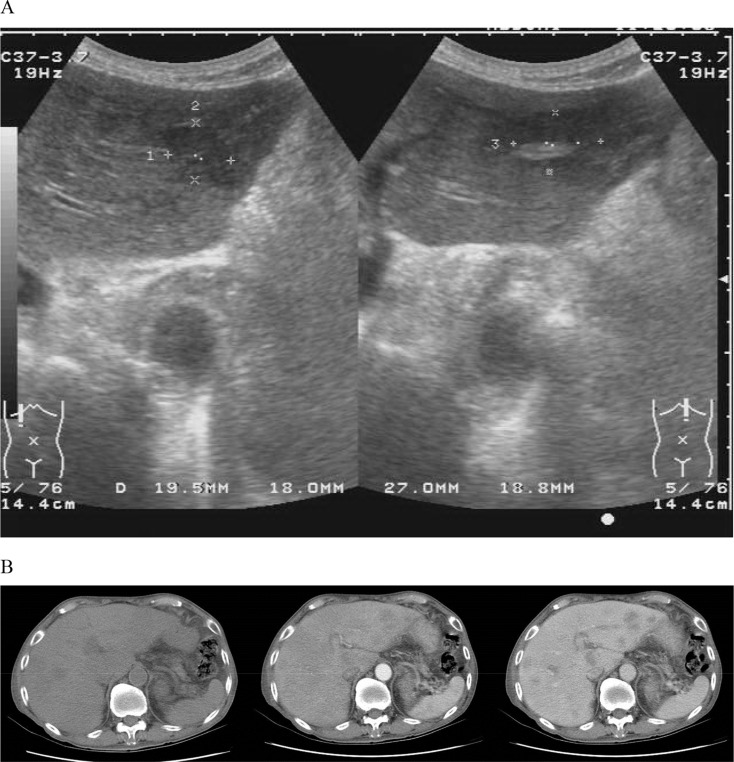

An 86-year-old man presented with intermittent fever for 1 month. He had dull abdominal pain in the right upper quadrant for 2 weeks. The patient denied a productive cough, chest pain, and dysuria. He had no recent travel history and no body weight loss. He had no underlying systemic disease, such as diabetes mellitus. Physical examinations were not remarkable. Laboratory data revealed leukocytosis (white blood cells: 21.34 × 103 /μL, neutrophils: 83.6%). Aspartate and alanine aminotransferase levels were 23 IU/L and 19 IU/L (normal range: < 31 IU/L), respectively, and total bilirubin was 0.3 mg/dL (normal range: 0.2–1.5 mg/dL). His alkaline phosphatase was 117 IU/L (normal range: 40–129 IU/L). Hepatitis B surface antigen and antihepatitis C viral antibody were nonreactive, and tumor markers (α-fetoprotein, carcinoembryonic antigen, prostate-specific antigen, and cancer antigen 19-9) were within normal limits. An initial chest radiograph showed no abnormalities. Because of sustained fever, abdominal ultrasonography (Fig. 1 A) and computed tomography (Fig. 1 B, from left to right: noncontrast, arterial phase, and delayed phase) were performed. What is your impression?

(A) Abdominal ultrasonography of the liver (left: right lateral lobe; right: left medical lobe); (B) computed tomography of the abdomen (from left to right: noncontrast image, arterial phase, and delayed phase of postcontrast images).